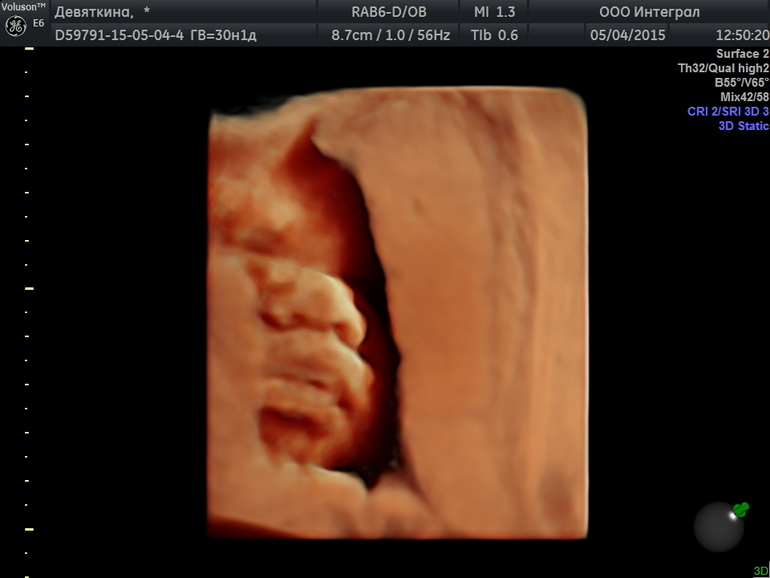

Целовательные фоточки Даниилушке!

Такие губки целовательные

Губки бантиком!